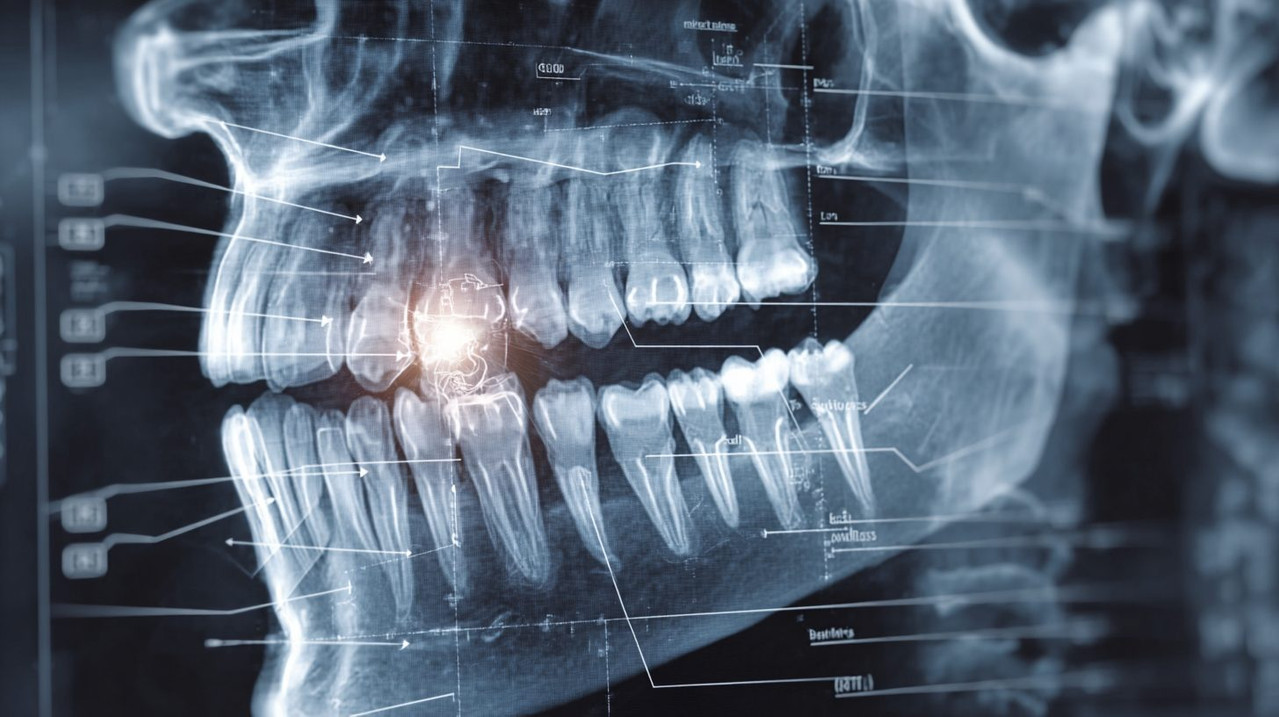

Киста зуба формируется как полостное образование в тканях вокруг корня зуба или в челюстной кости. Это состояние часто развивается незаметно и может оставаться без симптомов на ранних стадиях. В стоматологии такие случаи диагностируют с помощью рентгеновских исследований, что позволяет своевременного выявить проблему. Понимание природы кисты помогает осознать необходимость регулярных осмотров, поскольку игнорирование приводит к распространению инфекции и разрушению окружающих тканей.

- Рентгенография: стандартный метод в российских клиниках, позволяющий увидеть полость кисты как темное пятно у корня зуба.

Схема расположения кисты зуба на рентгеновском снимке, иллюстрирующая полостное образование у корня.

- Рентген: ортопантомограмма или прицельный снимок для визуализации кисты как округлого просветления.